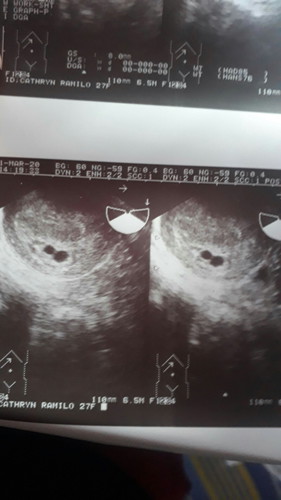

Pasama nman po ako sa prayers nyo. Sna mging okay cla. Spotting po kc ako kya need bedrest ng 3weeks. need ko dn ng prayers pra mg survive clang dlawa. 4weeks & 5days. Thank you ?

Ndi ko po expected my twins. Kc po wla nman sa lahi nmen. Pg pray dn po kta. 🙏

Kht dn po sa partner ko wla dn cla lahi na twins. Sana ibigay na sken to ni lord. Kc cs ako sa first baby ko. Pra tgil na tlga. 😅